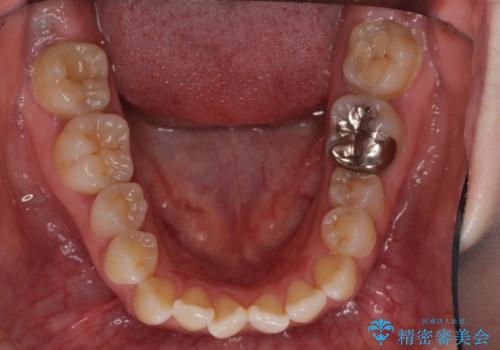

口元の突出感を改善 インビザラインによる非抜歯矯正

- 前歯がデコボコした上に口元が閉じにくいことを気にして来院された患者様です。

IPR(歯と歯の間を削る)と側方拡大では口の閉じにくさは改善できそうになく、一方で抜歯矯正を行うほどの突出感は認められませんでした。

親知らずを全て抜去し、歯列全体を後方に移動させることで口元の閉じにくさいを改善していくこととしました。

インビザラインでの歯列全体の後方移動は時間がかかりますが、しっかりと装着時間を守っていただいたので、スッキリとした口元に仕上げることができました。